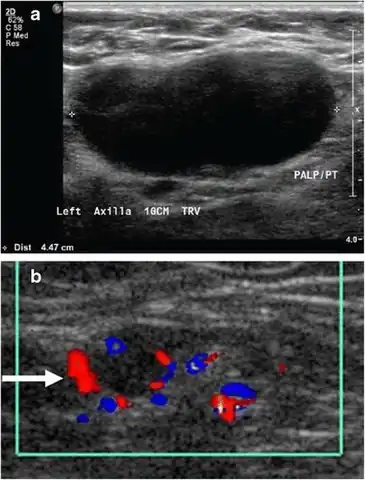

- Absence of the fatty hilum

- Increased focal cortical thickness greater than 3 cm

- Doppler ultrasonography that shows hyperaemic blood flow in the hilum and central cortex and/or abnormal (non-hilar cortical) blood flow.[26]

On ultrasound, B-mode imaging depicts lymph node morphology, whilst power Doppler can assess the vascular pattern.[28] B-mode imaging features that can distinguish metastasis and lymphoma include size, shape, calcification, loss of hilar architecture, as well as intranodal necrosis.[28] Soft tissue edema and nodal matting on B-mode imaging suggests tuberculous cervical lymphadenitis or previous radiation therapy.[28] Serial monitoring of nodal size and vascularity are useful in assessing treatment response.[28]

Lymphadenopathy of the axillary lymph nodes can be defined as solid nodes measuring more than 15 mm without fatty hilum.[36] Axillary lymph nodes may be normal up to 30 mm if consisting largely of fat.[36]